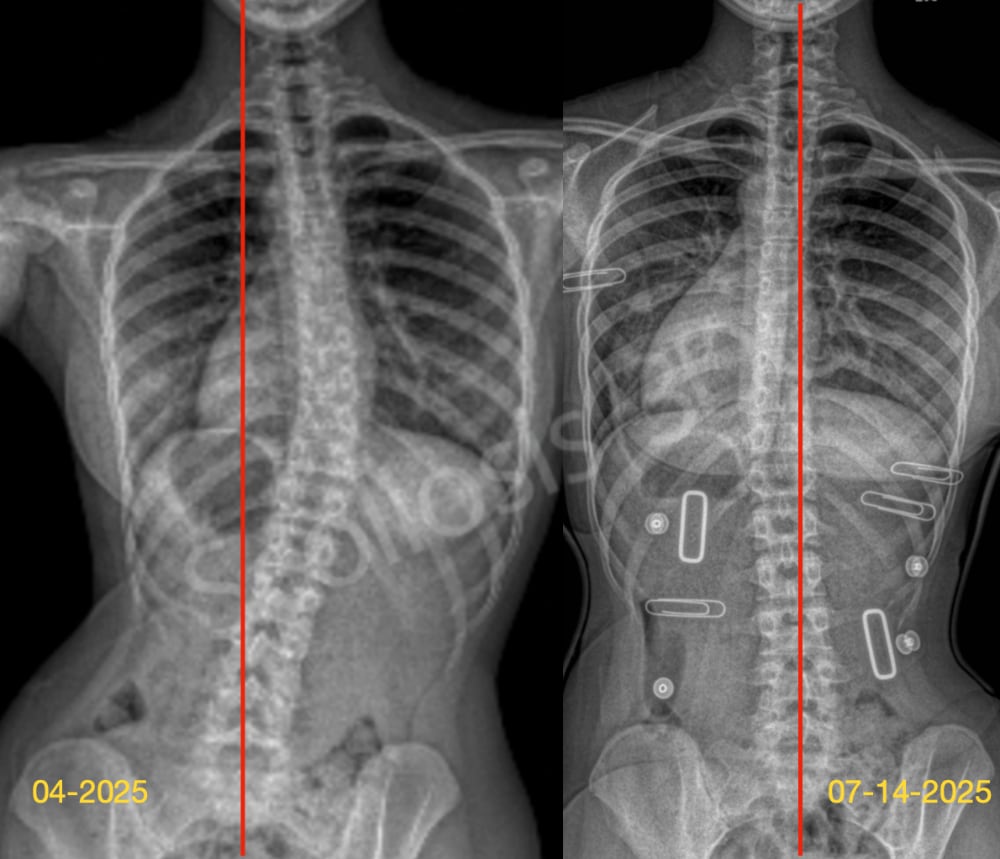

تقييم اعوجاج العمود الفقري بعد 6 أشهر بدون الحزام: أهم مؤشر لتحديد نجاح العلاج…

تقييم اعوجاج العمود الفقري بعد 6 أشهر بدون الحزام: أهم مؤشر لتحديد نجاح العلاج يُعد اعوجاج العمود الفقري لدى المراهقين من أكثر الحالات التي تُقلق الأهل، خاصة عند بدء العلاج بالحزام الطبي (الدعامة). وغالبًا

التنبؤ بنتائج حزام اعوجاج العمود الفقري :الفرق بين الأشعة داخل الحزام وخارجه…

التنبؤ بنتائج حزام اعوجاج العمود الفقري :الفرق بين الأشعة داخل الحزام وخارجه يُعد اعوجاج العمود الفقري عند المراهقين من أكثر حالات التشوهات الشائعة خلال مرحلة النمو، ويُعرف طبيًا باسم “الجنف مجهول السبب عند المراهقين”.